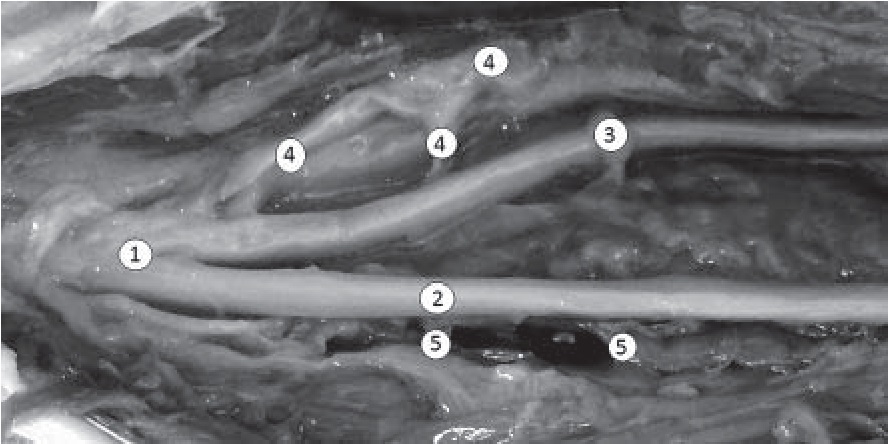

Далее, после входа в верхний мышечно-малоберцовый канал, нерв делится на свои конечные ветви – поверхностную и глубокую. Сразу после входа в туннель, помимо двух основных ветвей, он отдает от 2 до 5 ветвей, которые проникают в верхнюю часть длинной малоберцовой мышцы. Как правило, всегда имеются одна крупная ветвь и 2–3 мелкие веточки, не имеющие между собой анастомозов. Во всех случаях в этой области отходят 1–2 постоянные ветви, иннервирующие капсулу коленного сустава. Кроме того, в этой области наблюдается «рассыпной» тип деления нерва. Какой-либо вариабельности разветвления нерва в этой области не отмечено, за исключением разного количества мелких ветвей. Тем не менее именно факт наличия этих ветвей не позволяет провести адекватную мобилизацию дистального фрагмента при повреждении нерва на уровне головки малоберцовой кости (рис. 4).

Рис. 4. Деление общего малоберцового нерва на конечные ветви: 1 – ствол общего малоберцового нерва; 2 – поверхностный малоберцовый нерв; 3 – глубокий малоберцовый нерв; 4 – ветви, иннервирующие малоберцовую мышцу; 5 – ветви к капсуле коленного сустава

Диаметр глубокого малоберцового нерва в месте его формирования составляет 4,2±1,2 мм. На всех изученных объектах глубокий малоберцовый нерв имеет концентрический тип строения: по ходу про- хождения основного ствола к иннервируемым мышцам от него отходят мелкие ветви диаметром около 2 мм: в верхних отделах – от 3 до 5 ветвей к передней большеберцовой мышце, около 15 ветвей – к длин- ному разгибателю пальцев и длинному разгибателю большого пальца (рис. 5). Как и у поверхностного малоберцового нерва, дальнейшее деление глубокого малоберцового нерва не отличается существенной вариабельностью.

Рис. 5. Продвижение глубокого и поверхностного малоберцовых нервов: 1 – ствол общего малоберцового нерва; 2 – глубокий малоберцовый нерв; 3 – поверхностный малоберцовый нерв; 4 – ветви, иннервирующие длинную малоберцовую мышцу; 5 – ветви, иннервирующие переднюю большеберцовую мышцу